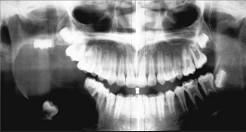

问题 男,18岁,右颌下区反复肿胀半年,2天前再次发作,病程进展快,出现张口受限。X线片示右下颌角区沿颌骨长轴有单囊阴影,包绕右下颌第三磨牙牙冠。该病人最可能的诊断是()

选项 A.右下颌造釉细胞瘤 B.右下颌角化囊肿继发感染 C.右下颌骨含牙囊肿 D.右下颌骨中央性癌 E.右下颌骨骨髓炎

答案 C